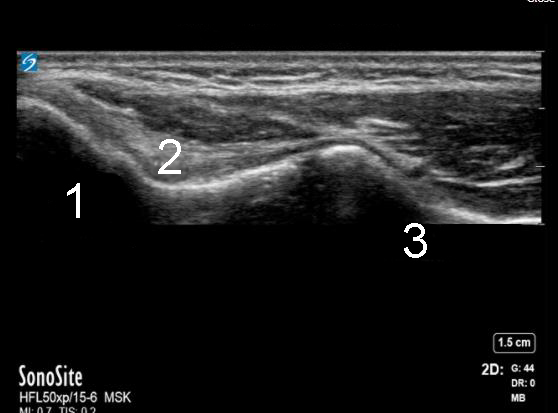

Elbow Medial Elbow Image

1. Medial Epicondyle

2. Ulnar Collateral Ligament (UCL)

3. Sublime Tubercle of the Ulna